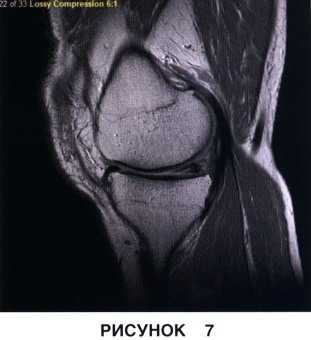

• Неполные разрывы в области верхней или нижней поверхности мениска (рис. 6 и 7)